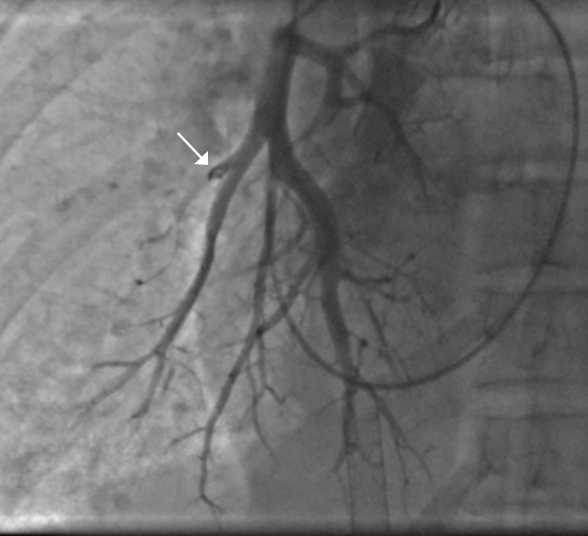

ЧКВ после 48 ч от начала ИМпST у бессимптомных больных с окклюзированной ИСА при объективизации жизнеспособного/ишемизированного миокарда

Современные регламентирующие документы не рекомендуют рутинно выполнять реканализацию окклюзированной ИСА у бессимптомных больных при сроке от начала ИМпST >48 ч [1, 2, 7]. В качестве доказательной базы этого утверждения приводятся данные рандомизированного исследования OAT [35, 36] и метаанализа Ioannidis JP, et al., 2007 [37], которые показали отсутствие пользы рутинной ЧКВ окклюзированной ИСА по сравнению с медикаментозной терапией для снижения риска смерти, реинфаркта, СН. Приведенные аргументы признаны рабочей группой рекомендаций достаточно убедительными, чтобы дать им самый высокий статус достоверности — А. Дальнейшая лечебная стратегия ведения стабильных больных с окклюзией коронарных артерий, выявленной в срок >48 ч от начала ИМпST, предусматривает подход с определением показаний к реканализации на основании оценки объема жизнеспособного миокарда, как это закреплено в рекомендациях по ведению пациентов со стабильной ишемической болезнью сердца [38]. Сроки выполнения данной стратегии не определены, некоторые центры выполняют ее в течение индексной госпитализации, но в большинстве случаев центры переносят практическую реализацию этого подхода на отдельную отсроченную госпитализацию.

В заключение разбора этой отдельной группы пациентов с поздним ЧКВ при ИМпST (бессимптомных, госпитализированных после 48 ч от начала заболевания, с зарегистрированной окклюзией ИСА, имеющих объективные доказательства жизнеспособного/ишемизированного миокарда) необходимо сказать, что, конечно, их эффективность уступает пЧКВ, но данные вмешательства могут выполняться и выполняются, а отсутствие доказательств пользы такого вида эндоваскулярных операций открывает дополнительные возможности для реализации амбиций интервенционных кардиологов на ниве научной деятельности.